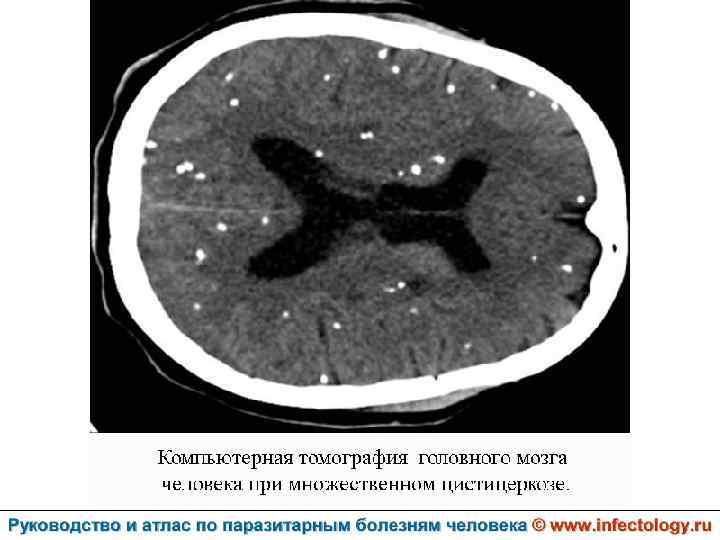

Цистицеркоз (шифр по МКБ 10 - B 69) – биогельминтоз, который вызывается паразитированием в тканях и органах человека и животных личиночной стадии цепня вооруженного – цистицерка (Cysticercus cellulosae) Болезнь проявляется разнообразными симптомами в зависимости от локализации цистицерков.